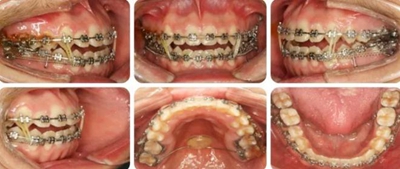

治療過程

6個(gè)月,上牙列擁擠得到解除。上下頜植入種植釘,用于上后牙壓低及下牙列遠(yuǎn)移。

14個(gè)月,前牙開頜得到改善,配合使用垂直牽引。

16個(gè)月,前牙開頜糾正。

結(jié)束時(shí),可見前牙覆合覆蓋正常,上下牙列排齊,雙側(cè)尖磨牙達(dá)到中性關(guān)系。